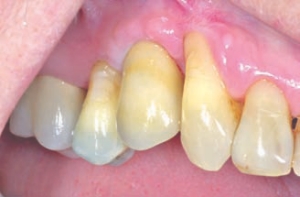

A Key Implant Position For A Fixed Prosthesis: The First Molar Rule

FIGURE 4--A panoramic radiograph from figures 2 and 3.

Treatment planning for implant dentistry in the posterior regions of the mouth is often driven by the existing bone volume in the edentulous sites. As a consequence, distal cantilevers are extended from anterior implants or shorter implants are placed in the posterior regions of the mouth. 1 In the maxillary posterior region, pterygoid and/or zygomatic … Read more